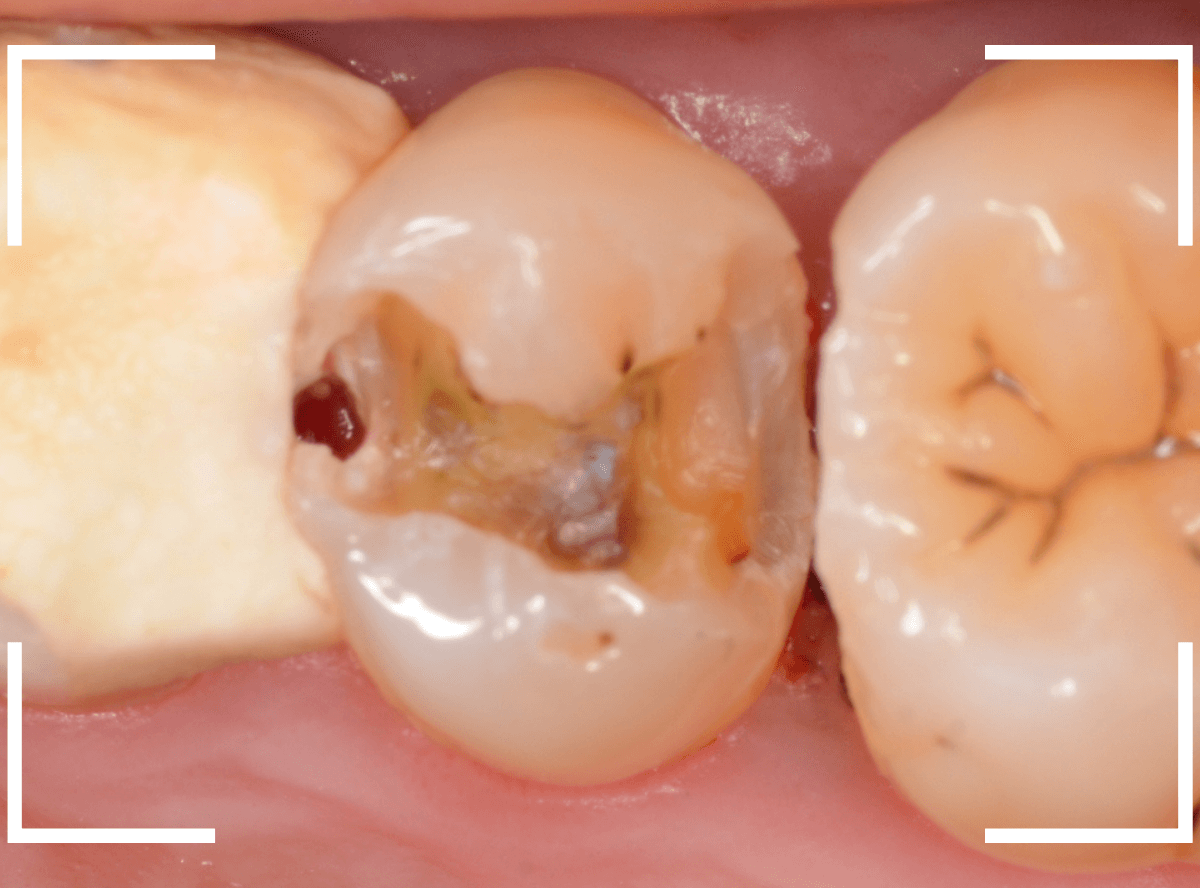

Case.21 神経に達しそうな2本の大きな虫歯

上の小臼歯の側面が明らかに虫歯になっている患者さんです。

患者さんは特に症状を感じてなさそうですが、恐らくは中で大きな虫歯になっているでしょう。

このように、自覚症状からだけでは虫歯の状況は診できません。

レントゲン写真で確認します。

青い線が歯の神経、赤い線が虫歯と思われる部分です。

2本とも、神経に達してしまいそうな大きな虫歯であると思われます。

まず、奥の歯のつめものを外してから、虫歯の治療を開始します。

手前の歯が大きな虫歯が見えてきました。

神経に達してしまいそうな虫歯ですので、ある程度削ったところで、少しずつエキスカという道具で掻き出すようにして、虫歯を除去します。

虫歯は歯を溶かして進行しますので、骨よりも固い歯もちょっと掻き出すとボロボロと崩れるようになってしまっています。

かなり虫歯を除去したところで、手前の歯は神経が顔を出してしまいました(露髄といいます)。

神経を除去する治療が必要かもしれないです。

全ての虫歯を除去したところです。

幸い、後ろの歯は薄皮一枚のところで神経まで達していない虫歯ですんでいましたが、大きな虫歯だった事には変わりありません。

いつものように、神経が痛み出さないように祈りつつ、お薬で保護して経過観察します。

虫歯は症状からだけでは判断できませんが、定期受診によって、このような大きな虫歯の処置は避けられる事がほとんどです。

かならず歯科の定期受診をしてくださいね。